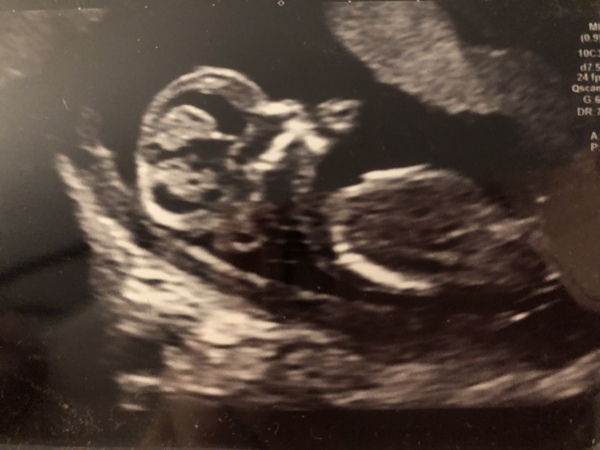

Here’s my little one at 15 weeks. We had a little scare so had a check up @ 15 weeks but all was good! We’ve so far had lots of girl guesses and 3 boy guesses (including my husband)! Very long legs as well, the more to kick me with haha